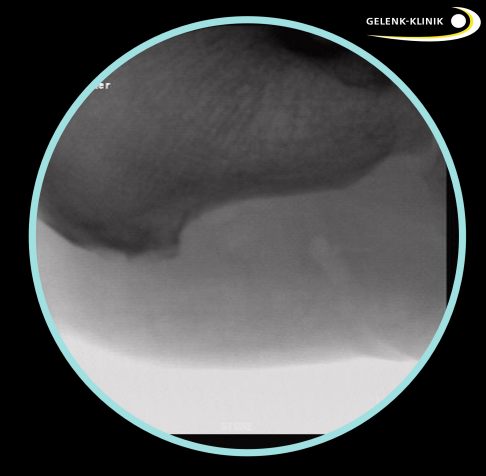

Unter Röntgenkontrolle mit einer beweglichen Röntgenröhre (Bildwandler) lokalisiert der Fußspezialist den Fersensporn und markiert ihn mit einer Nadel. Dann führt er über zwei kleine Hautschnitte eine Kamera mit Lichtquelle und spezielle chirurgische Instrumente ein. Durch die Nadelmarkierung kann der Fersensporn leicht gefunden und dargestellt werden. Mit einer kleinen Kugelfräse entfernt der Operateur den knöchernen Vorsprung. Dann glättet er das Fersenbein vollständig, um eine weitere Reizung und Entzündung der Sehnen zu verhindern.

Markierung des Fersensporns: Zunächst lokalisiert der Operateur den Fersensporn mit einem beweglichen Röntgengerät und markiert ihn mit einer Nadel. © Gelenk-Klinik